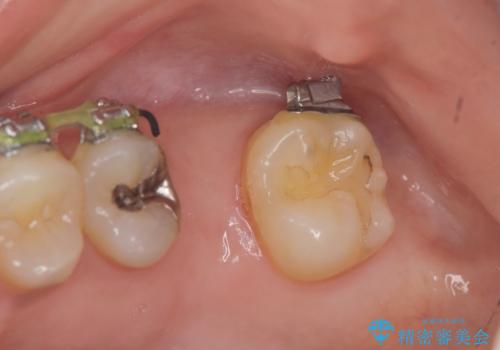

- 他院での矯正治療中、欠損した左上奥歯のインプラント治療を希望され来院されました。

最終的な歯の位置を矯正の担当医と綿密に相談しながら、インプラントの埋入部位を決定し治療にあたりました。

骨量が少なかったことから、上顎洞内へのソケットリフト方をインプラント埋入と同時に施行しています。